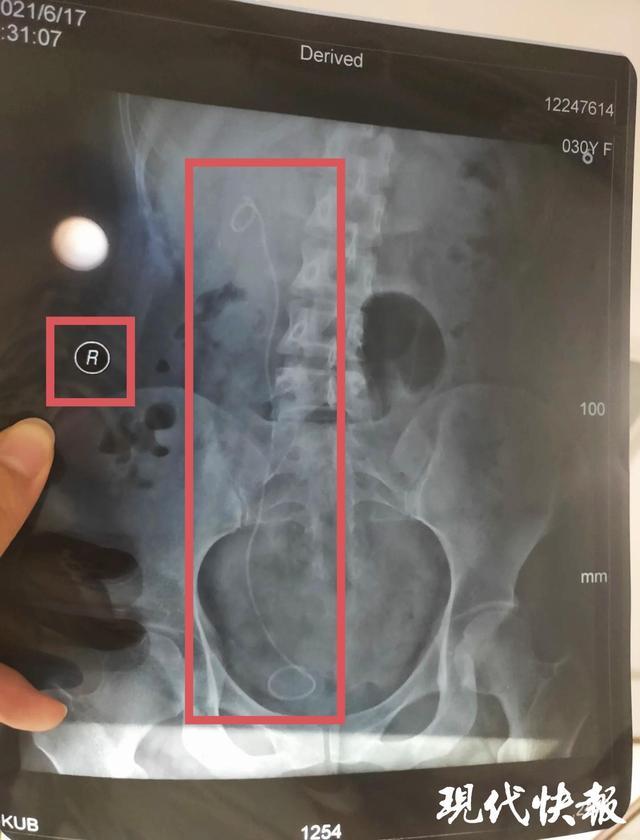

现代快报讯(记者 王瑞)手术前签订的知情同意书,明确对左侧输尿管进行检查和治疗,可手术后却发现,医生“左右不分”,竟然在右侧无异常输尿管中放入了一个支架管。后经医学相关部门鉴定,认定这是一起四级医疗事故,医院承担完全责任。

盐城市民朱女士因左侧输尿管狭窄伴左肾积水,前往复旦大学附属华山医院诊治,办好一系列手续后,2021年4月19日住院,4月21日签订手术知情同意书。手术知情同意书显示,拟对左侧输尿管镜检备扩张/内切开。直到出院一个多月后复查时,她才意外发现,手术期间,医生竟然“把左右给搞错了”,在右侧输尿管无异常的情况下,医生在右侧输尿管内安装了支架管。